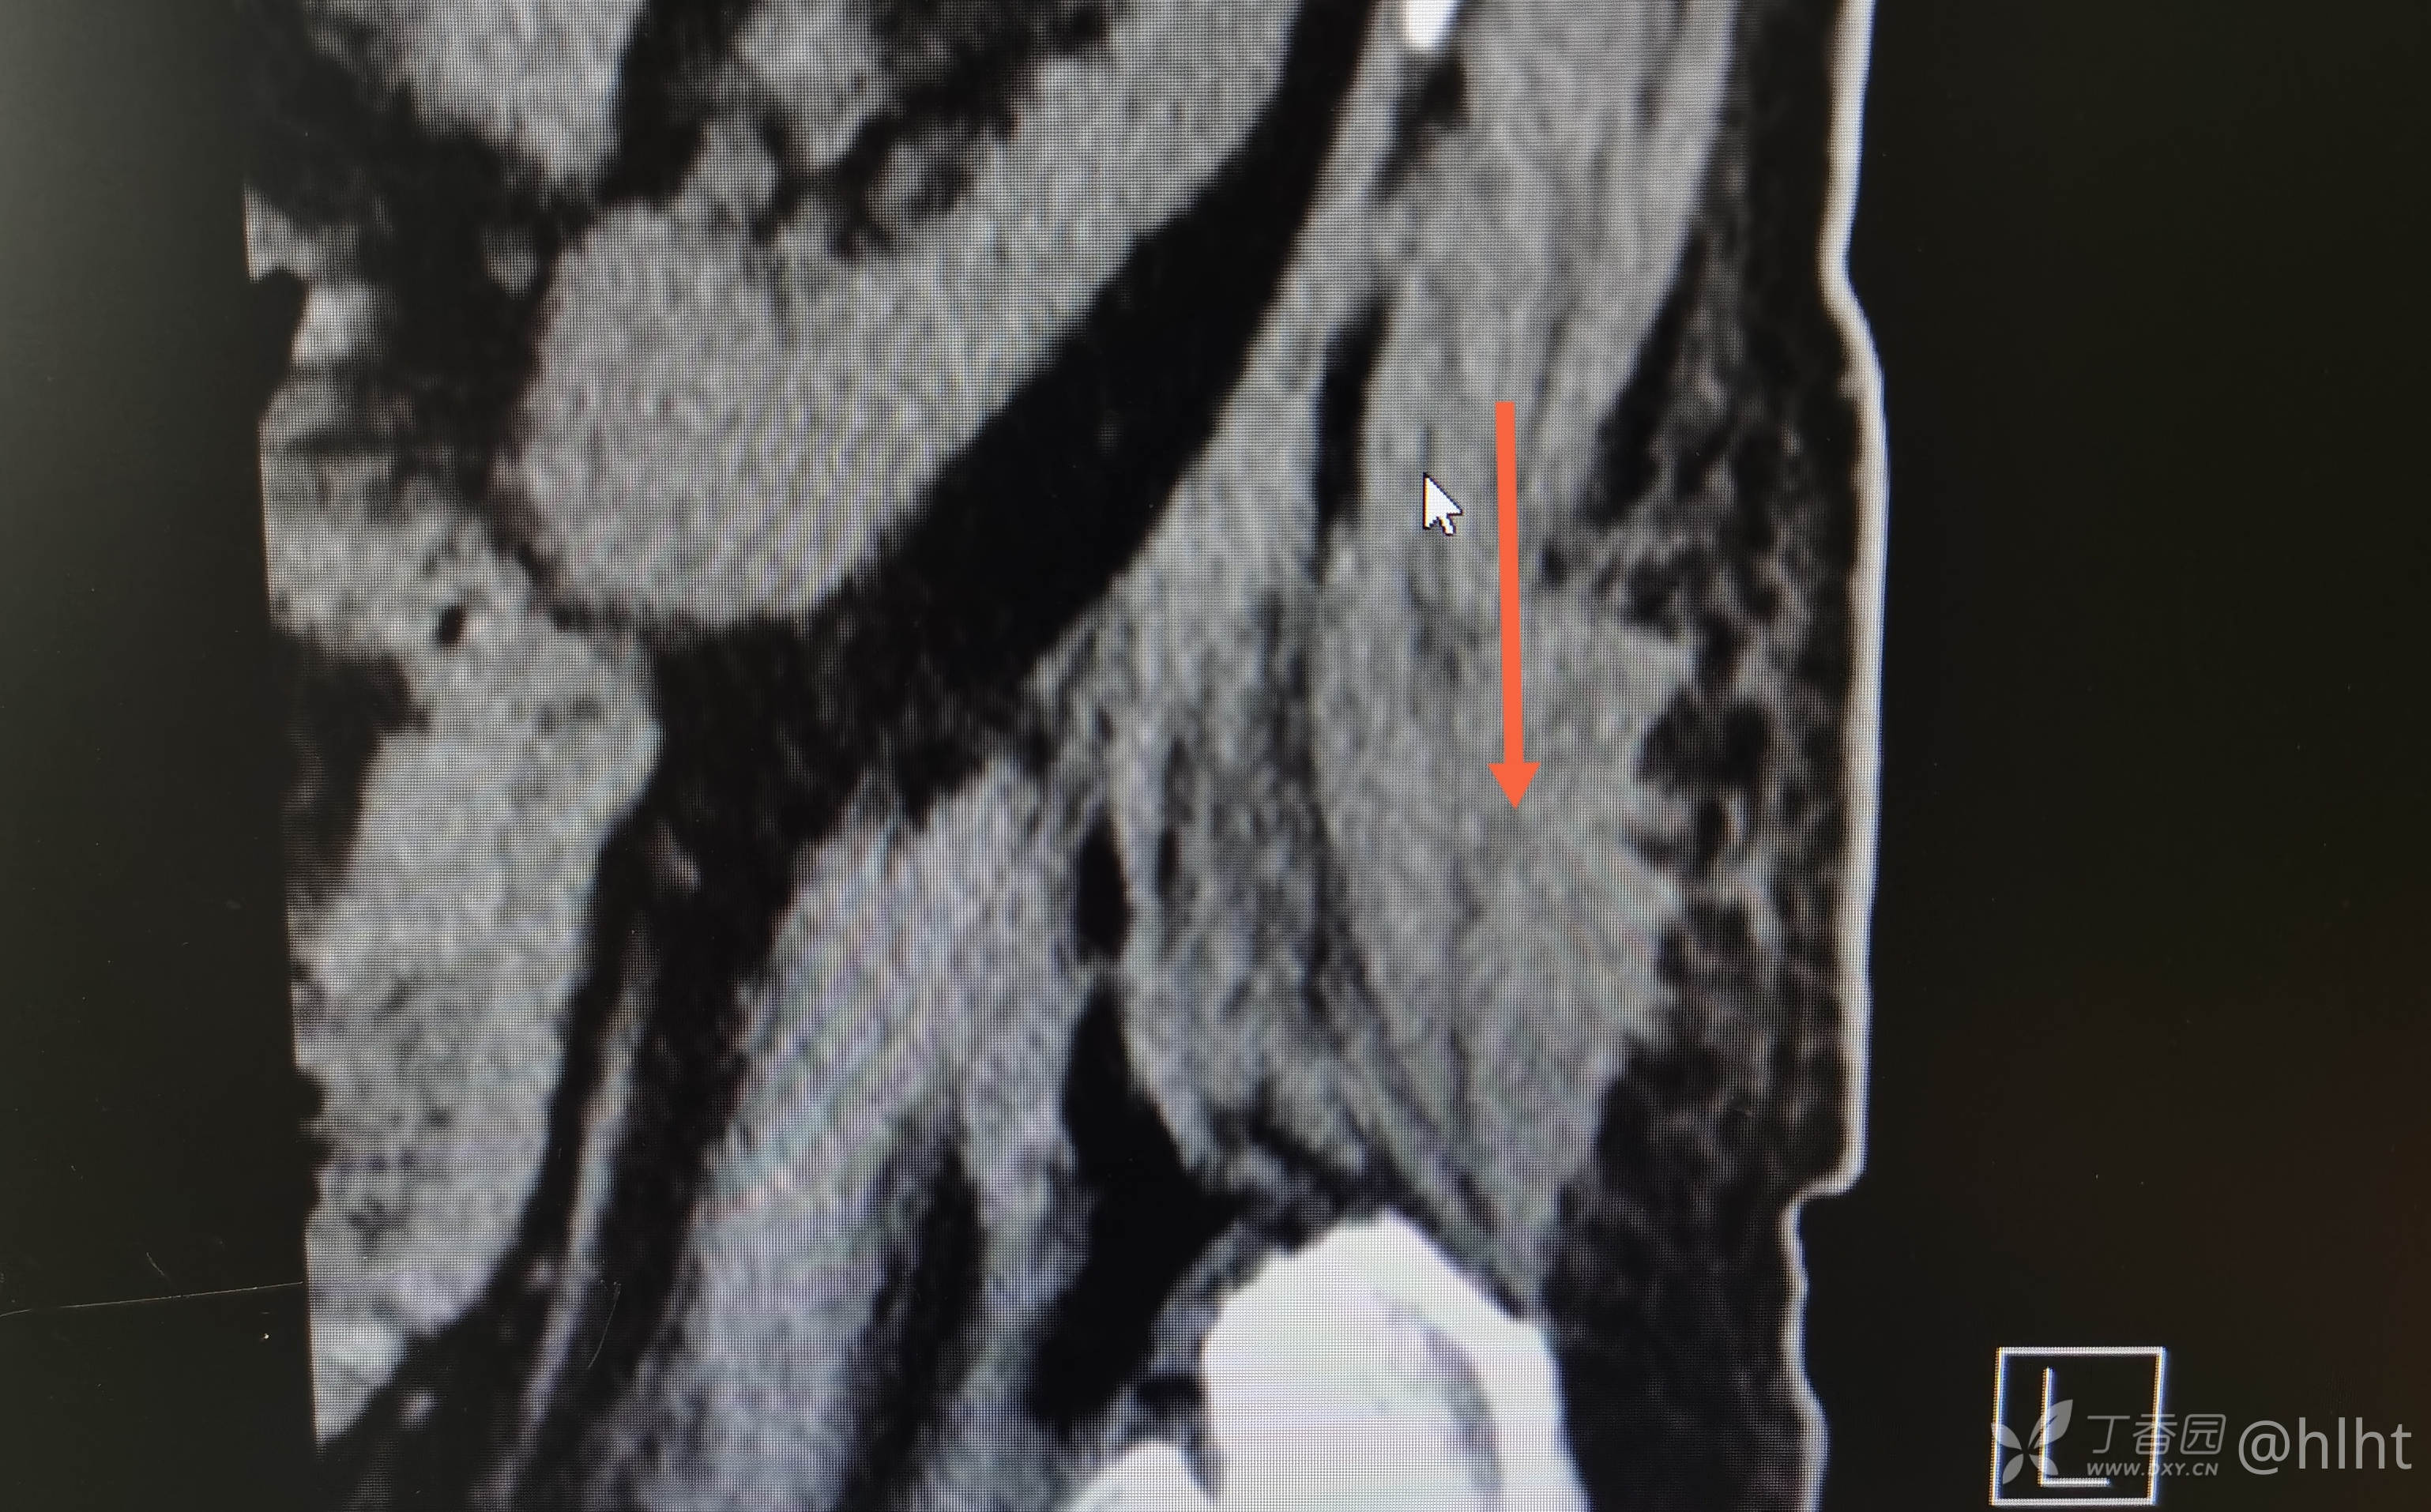

诊断:1.左侧腰大肌、髂腰肌脓肿 :结核? 2.2型糖尿病 3.高血压2级